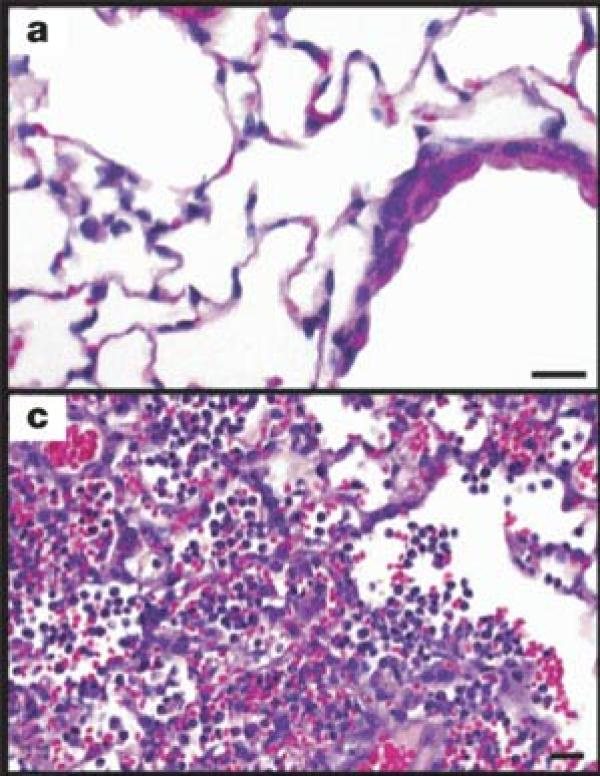

图C显示了1918病毒对小白鼠肺组织的影响

科学家另外进行了实验来确定1918病毒感染是否还会扩散到小白鼠的其他重要器官,例如脑、心、肝和脾脏。实验室检测没有在这些器官中发现病毒,说明1918病毒不会对病人造成系统感染。当年1918病毒广泛记载的影响是肺部严重迅速的损害。1918疫情中的病人有肺部充液、严重肺炎和肺组织炎症。在四天之内,感染1918病毒的小白鼠也具有类似的肺部并发症,说明这是1918病毒严重性的独具特征。